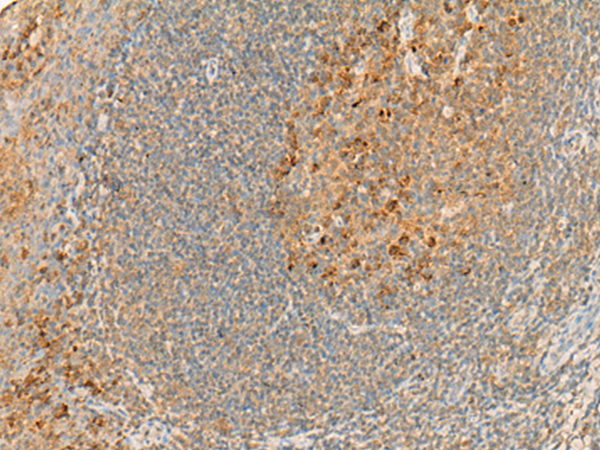

分类: 科研抗体货号: P13472别名: GBT1; GNATR; CSNB1G; CSNBAD3应用: WB,IHC反应种属: Human, Mouse